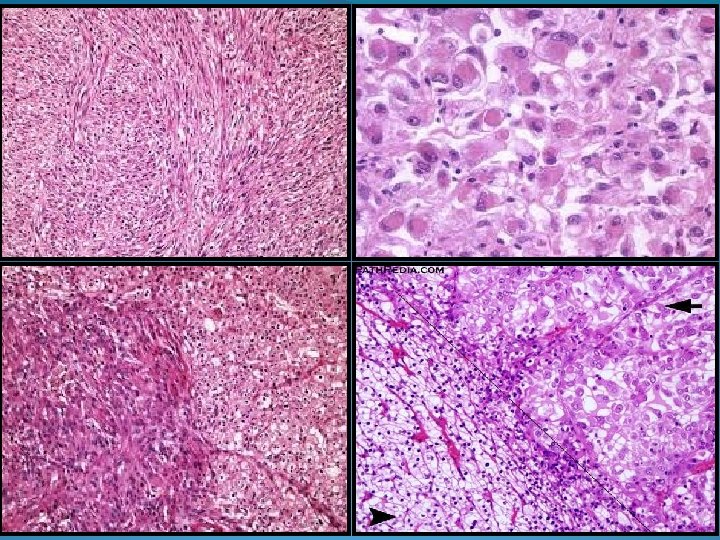

Risultati dell’indagine relativa all’applicazione del grading In base a quali caratteristiche definisci la presenza di una componente sarcomatoide? • • Allungamento delle cellule epiteliali (3%) Presenza di cellule fusate (22%) Presenza di cellule fusate atipiche, simil-sarcomatose (41%) Presenza di cellule atipiche, simil-sarcomatose, anche in assenza di morfologia fusocellulare (34%) Non si raggiunse un consensus Tuttavia la maggioranza dei partecipanti (41%) definì sarcomatoide un RCC con una componente di cellule fusate atipiche, similsarcomatose

Risultati dell’indagine relativa all’applicazione del grading In un RCC con componente sarcomatoide specifichi nel referto l’istotipo tumorale sottostante? • • Si (94%) No a) Aree di dediffernziazione sarcomatoide possono ritrovarsi in ogni istotipo con frequenza differente (CD-RCC: 25 -29%; CC-RCC: 5, 2 -8%; Ch-RCC: 2 -9%; PRCC: 1, 9 -5, 4%). b) L’istotipo sottostante non impatta sulla prognosi. c) Nelle metastasi di RCC sarcomatoide può ritrovarsi la sola componente carcinomatosa sottostante. d) Ci può essere, seppur modesta, una migliore risposta alla terapia con inibitori della tirosin-chinasi o con bevacizumab negli RCC sarcomatoidi con sottostante componente di CC-RCC rispetto a quelli non CC-RCC (dato da validare in più ampi trials clinici randomizzati, prospettici).

Risultati dell’indagine relativa all’applicazione del grading Per segnalare la presenza di una componente sarcomatoide è necessaria una % minima? • • Si No (71%) Come definisci un RCC con morfologia sarcomatoide pura? • • RCC inclassificato con componente sarcomatoide RCC di grado 4 RCC inclassificato con componente sarcomatoide, grado 4

Risultati dell’indagine relativa all’applicazione del grading Segnali nel referto la presenza di una componente rabdoide? • • Si (74%) No In un RCC con componente rabdoide specifichi nel referto l’istotipo tumorale sottostante? • • Si (99%) No Per definire la presenza di una componente rabdoide è necessaria una % minima? • • Si No (79%) Come definisci un RCC con morfologia rabdoide pura? • • • RCC inclassificato con componente rabdoide, grado 4 RCC di grado 4

Grading WHO/ISUP • Grado 1: nucleoli invisibili o incospicui e basofili a 40 x. • Grado 2: nucleoli chiaramente visibili a 40 x, invisibili o incospicui a 10 x. • Grad 0 3: nucleoli eosinofili e chiaramente visibili a 10 x. • Grado 4: estremo pleomorfismo nucleare e/o cellule giganti e/o qualsiasi % di componente sarcomatoide e/o rabdoide. Carcinoma a cellule chiare (78%) Carcinoma papillare (84%) Carcinoma cromofobo (78%) Eterogeneità di grado riportare il grado peggiore (almeno 1 HPF)

Grading WHO/ISUP validato come indicatore prognostico per CC -RCC e P-RCC Seppur non validato come indicatore prognostico per gli altri istotipi di RCC, può essere usato per descriverne le caratteristiche morfologiche